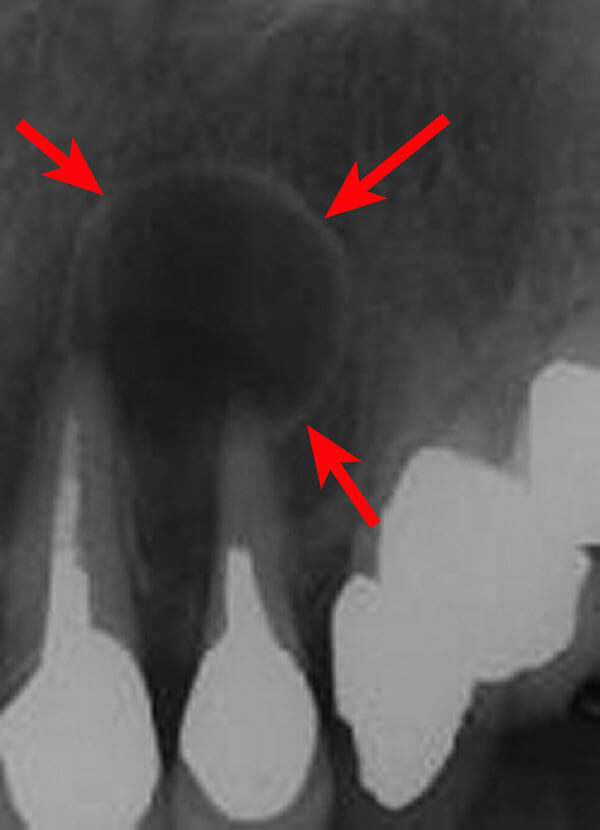

<歯根嚢胞に対する歯根端切除術+嚢胞摘出術>

歯の根の先に嚢胞ができ、歯茎に膿の出口を形成しています。